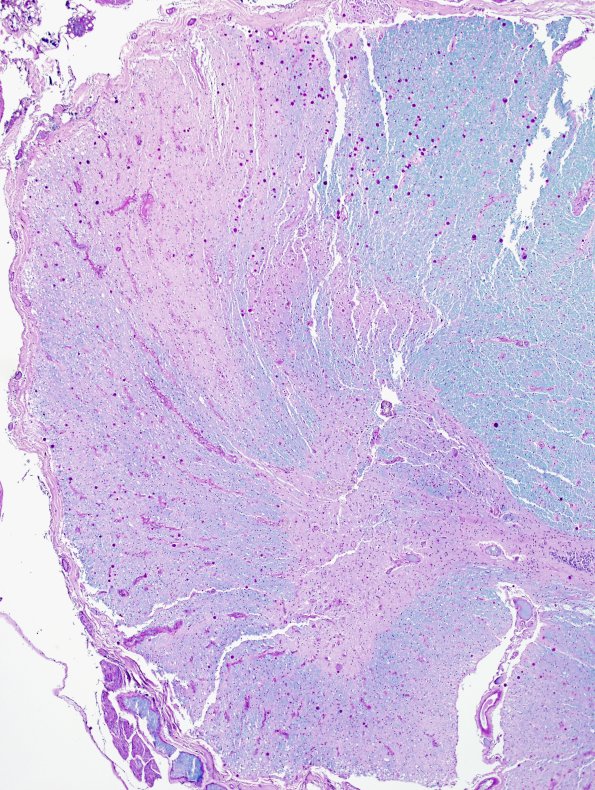

15F2 FTLD-ALS (Case 15) LFB-PAS N10 1A

Degeneration of the lateral corticospinal tract (LFB-PAS)